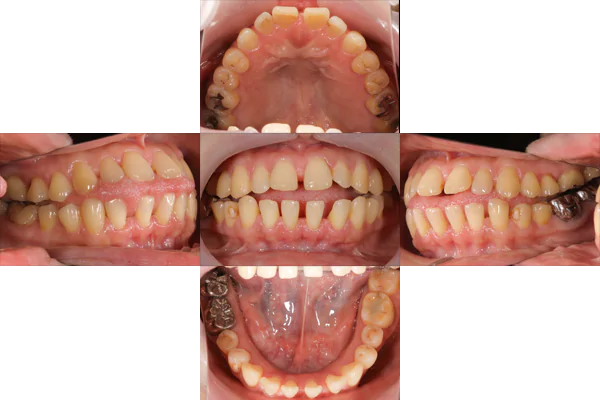

治療前

治療後